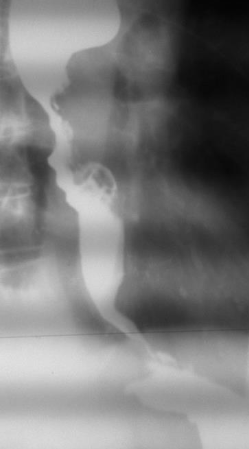

Achalazia cardiei